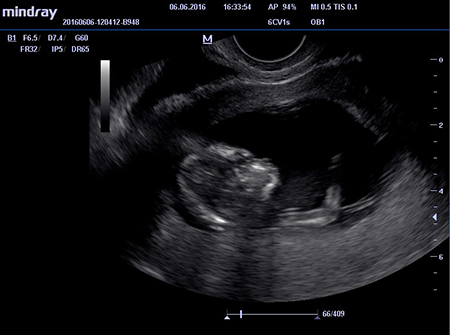

Первое плановое УЗИ проводится на 10-14 неделе беременности. В ходе обследования доктор получает информацию о плоде и материнских органах, поддерживающих жизнедеятельность малыша. Повторное обследование, как правило, назначается на 18-22 неделю беременности. На данном этапе можно точно определить пороки развития малыша и обозначить методы коррекции имеющейся патологии. Третье обязательное УЗИ плода при беременности проводится на 30-34 неделе срока. Результаты обследования позволят определить дату родов и возможность родить естественным путем или с помощью кесарева сечения.